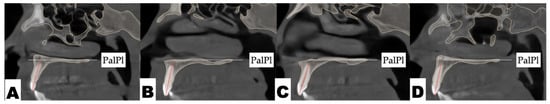

2.3.1. Surgical Protocol

2.3.2. Design of 3D Surgical Guide

2.3.3. Osteotomy Planning and Appliance Design

2.3.4. Postoperative Assessment, Outcome Analysis, and Asymmetry Correction